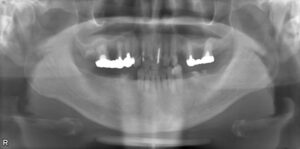

上顎4本欠損症例

BEFORE AFTER 63歳女性/上4本欠損/インプラント埋込手術 【治療内容】 数年前に数本抜歯したまま欠損補綴を…